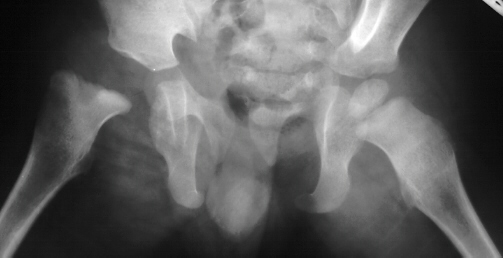

- Post Operative Day 18: R hip Xray: subluxation of R hip, possible metaphyseal

lucency consistent with osteomyelitis. Taken to OR for repeat I & D

of R hip via posterior approach with Penrose drains and hip spica cast

(15cc seropurulent fluid drained). Antibiotics changed to Oxacillin 225mg

IV q4.

Institute. Initial labs: WBC 15,100, ESR 72. R hip Xray: changes in proximal

. metaphysis including lucency and demineralization, hip subluxated. Treated

with oxacillin and Pavlik harness.

- 2 month Office Follow Up: Rt hip Xray: progressive destruction of capital

femoral epiphysis, cystic changes in metaphysis consistent with AVN.